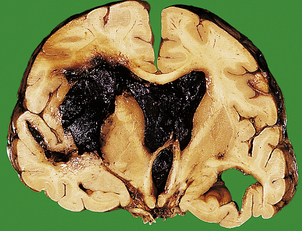

Intracerebral haemorrhage

The commonest cause of intracerebral haemorrhage is hypertensive vascular disease, in which haemorrhages occur most frequently in the basal ganglia (80% of cases), the brainstem, cerebellum and cerebral cortex. Most intracerebral haemorrhages occur in hypertensive adults over 50 years of age. The haematoma acts as a space-occupying lesion, causing a rapid increase in intracranial pressure and intracranial herniation (Fig. 26.11). In survivors, resorption of the haematoma eventually occurs, and a fluid-filled cyst with a gliotic wall is formed. The mortality from spontaneous intracerebral haemorrhage is greater than 80%, and many survivors suffer severe neurological deficit.

image

Fig. 26.11 Complications of intracerebral haemorrhage. An intracranial haemorrhage originating in the internal capsule on the left has ruptured into the ventricular system, which is filled with blood. The mass effect of the haematoma has resulted in a shift of adjacent structures to the opposite side.

The pathogenesis of spontaneous intracerebral haemorrhage is not fully understood. For many years, it was thought that most intracerebral haemorrhages in hypertensive patients occurred following rupture of micro-aneurysms on small arterioles, particularly on the lenticulostriate branch of the middle cerebral artery. Recent studies, however, have found that the ruptured vessels are arterioles, which show replacement of smooth muscle by lipids and fibrous tissue (lipohyalimosis), predisposing to rupture. Intracerebral haemorrhage in children and younger adults may occur as a consequence of trauma, or rupture of an arteriovenous malformation. In older adults, haemorrhage into the lobes of the brain may be due to amyloid depostion in the vessel walls (amyloid angiopathy), which is associated with Alzheimer’s disease (p. 779).